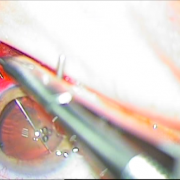

Μεταγχειριτική παρεκτόπιση ενδοφακού sun set syndrome

Μετεγχειριτική παρεκτόπιση ενδοφακού

Sun Set Syndrome

Συραφή του ίδιου φακού πίσω από την ίριδα

Συραφή του ίδιου φακού

πίσω από την ίριδα

Ευθυγραμμισμένος ενδοφακός

Cat Gionni Ring

Τραυματική διάσπαση ζίνειου ζώνης 5 ωρών

Τραυματική διάσμαση ζήνειου

ζώνης 5 ωρών

Τοποθέτηση ειδικού δαχτυλίου

Φακοθρυψία

Τοποθέτηση αναδιπλούμενου φακού

Τοποθέτηση αναδιπλούμενου

φακού

Τελικό αποτέλεσμα